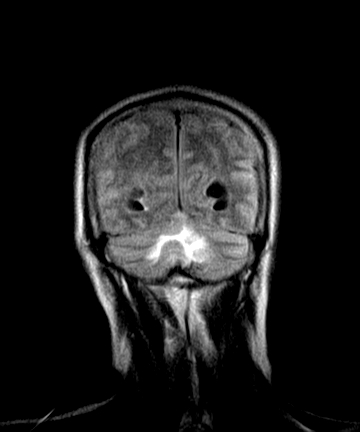

标题: MRI2064:少见病例。男性52,视力下降多年。 [打印本页]

标题: MRI2064:少见病例。男性52,视力下降多年。

四脑室区见混杂信号占位影,脑室系统扩张明显,临近结构显著受压称位,患者52岁,多考虑室管膜瘤可能性大

考虑第四脑室室管膜瘤并阻塞性脑积水。

考虑第四脑室室管膜瘤并梗阻性脑积水;部分性空蝶鞍;左侧上颌窦粘膜下囊肿。

考虑第四脑室室管膜瘤【血供丰富血管母细胞瘤可能】并梗阻性脑积水;部分性空蝶鞍;左侧上颌窦粘膜下囊肿。

比较典型的脉络丛乳头状瘤并脑积水,鉴别小脑蚓部血管母细胞瘤。